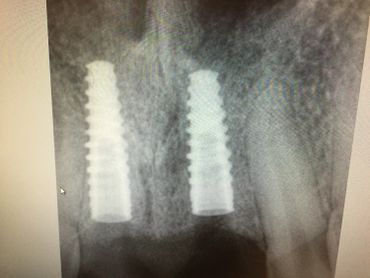

The Neodent GM Guided Surgery Kit is a compact, easy to use guided surgery system. Clinicians can provide CT scan, digital photos, and impressions to a laboratory for precise implant guide fabrication. Temporary teeth can be made and the lab will know the depth, angle, and timing of the connection of the implant. This allows you better esthetics and provides the patient teeth the same day with less chair time.

The Dental Future Center, Dr Bernee Dunson, and 3DDX Implant Guided Surgery course.